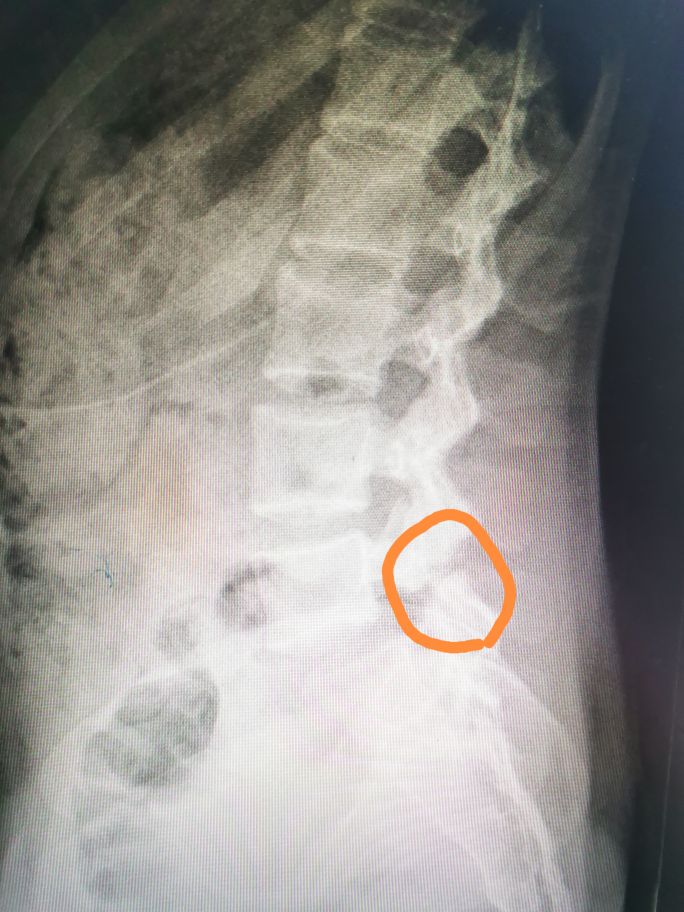

这样说比较抽象,其实最简单的办法就是把椎体分为四等份,超出1/4就是I度滑脱,超出2/4就是II度滑脱,依次类推。具体到这个病人,她上位椎体超出下位椎体1/4,那就是I度滑脱。那这个病人为什么会滑脱呢,也就是她属于何种类型的滑脱呢?首先她年纪很轻,不可能是退变性滑脱,大家看她的x线片:

圈子里面标记的部位是椎弓根峡部,大家看她的椎弓根那里已经断了,所以她这个属于椎弓根峡部裂导致的滑脱,也就是真性滑脱(椎弓根未断的滑脱是假性滑脱)。